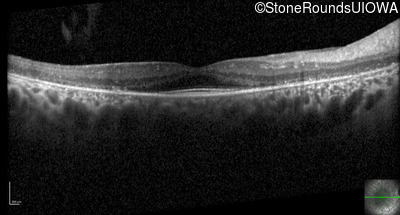

Optical Coherence Tomography - Left - 20/32 -1

Exemplar / OCT Stack